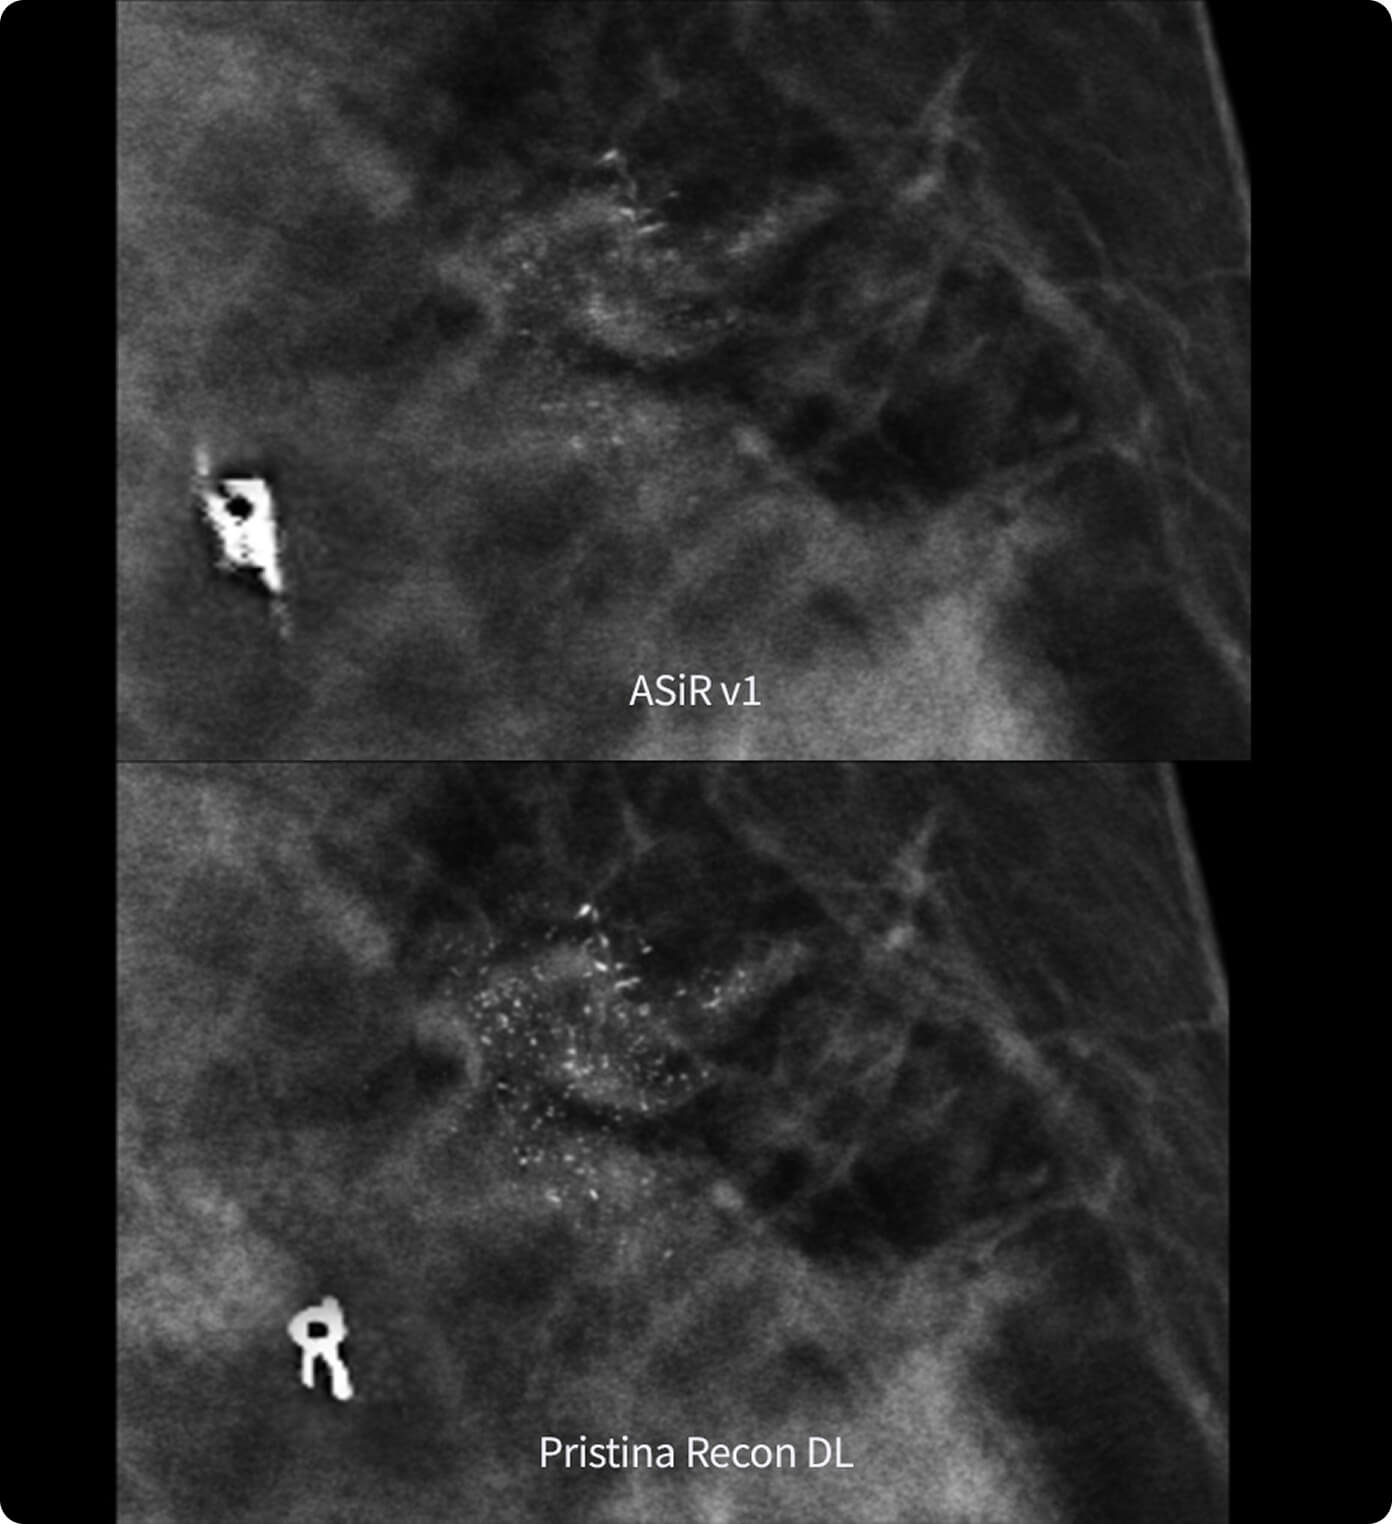

Reveals fine details minimizing artifacts and perceived noise1

Sharpness and overall IQ preferred in more than 99% of the image reviews1

In the detection of microcalcification clusters with modeled clinical data2

Its dual deep learning technology reveals fine details minimizing artifacts and perceived noise1,2, without increasing dose.

The improvement is easy to see, with radiologists surveyed consistently preferring its sharpness1,2 and lesion conspicuity1,2.

1. Preference study performed on 140 study cases with 8 MQSA-approved radiologists, trained on clinical image quality by ACR, comparing Pristina Recon DL to ASiR v1.

2. Reader performance evaluation on 19 680 reads with 8 readers using modeled clinical data comparing Pristina Recon DL and ASiR v1.